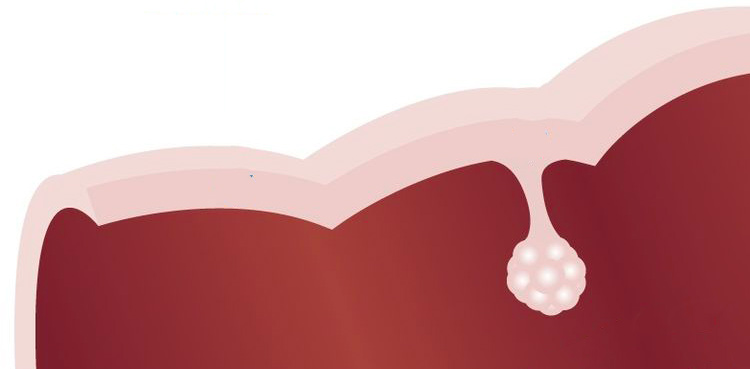

La breve durata di quelle cellule è essenziale, perché hanno a che fare con sostanze potenzialmente pericolose che potrebbero causare mutazioni nel loro DNA. Il processo non è ancora completamente chiaro, ma l’ipotesi più condivisa è che errori nella copia del materiale genetico quando queste specifiche cellule si moltiplicano facciano sì che non durino poco come dovrebbero. È una condizione anomala che di solito viene rilevata dal sistema immunitario, che provvede a distruggerle, ma in alcuni casi questo non avviene e si formano aggregati cellulari nell’epitelio: i polipi. Non sono tecnicamente un tumore maligno, nel senso che non si diffondono nei tessuti circostanti, ma se rimangono a lungo e continuano a crescere aumentano le probabilità che si accumulino ulteriori mutazioni nel materiale genetico delle cellule e che si arrivi al carcinoma vero e proprio, con una probabilità che questo si diffonda altrove.

Rappresentazione schematica di un polipo nel colon retto (Wikimedia)

Con la colonscopia si può andare alla ricerca di questi polipi ed eliminarli chirurgicamente, prima che si mettano a fare danni (anche se non è detto che questo succederebbe). Chi si deve sottoporre a una colonscopia deve seguire una preparazione che richiede l’assunzione di una sostanza, non molto piacevole da bere, che svuota e ripulisce il colon. Elimina tutto il suo contenuto rendendo piuttosto drastiche alcune sedute in bagno.